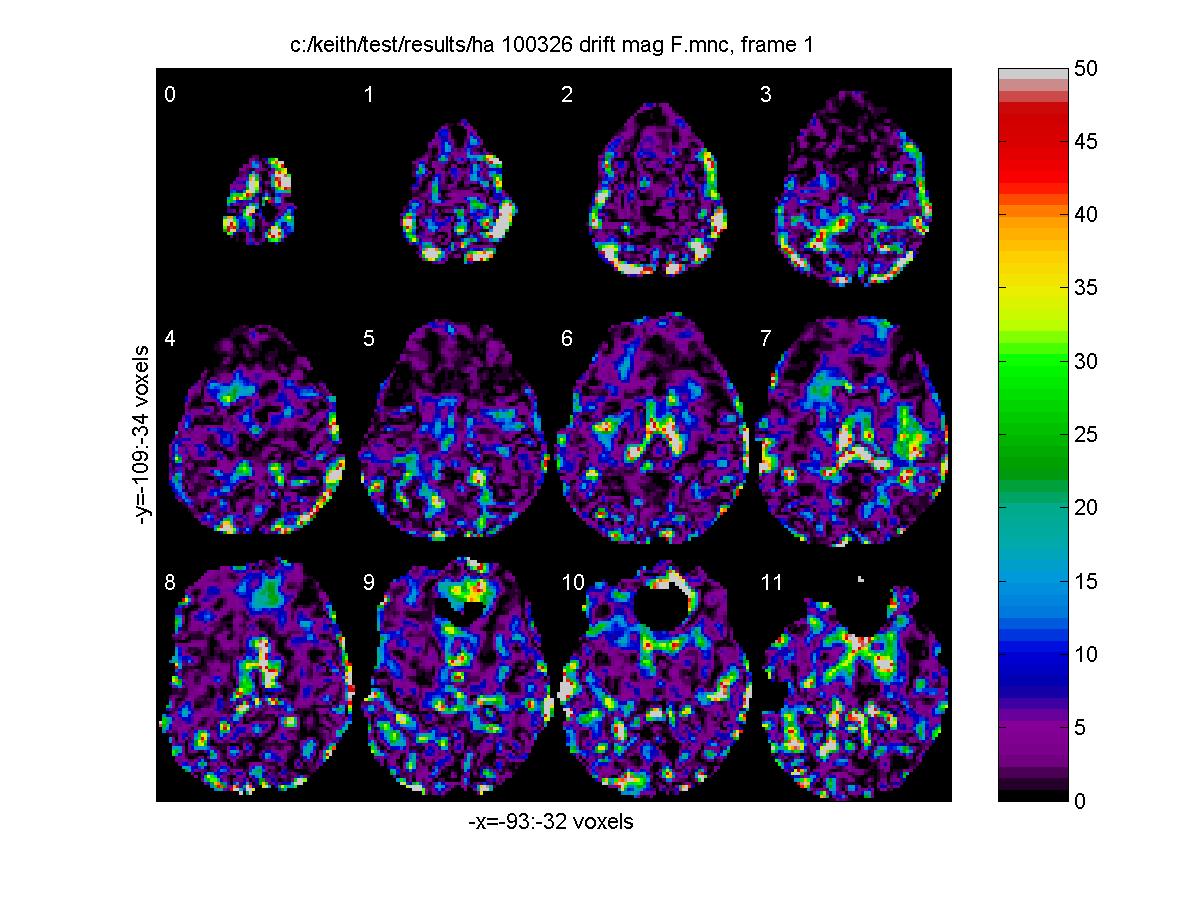

F-tests should only be used when we are interested in any linear combination of the contrasts. For example, an F-test would be appropriate for detecting regions with high temproal trend or drift, since we would be interested in either a linear, quadratic or cubic trend, or any linear combination of these. The drift terms appear in the order constant, linear, quadratic, cubic etc. so to test for a drift, use 'contrast.T' (T for temporal trend) as follows: contrast.T=[0 1 0 0; 0 0 1 0; 0 0 0 1] which_stats='_mag_F'; output_file_base='c:/keith/test/results/test_100326_drift'; fmrilm(input_file,output_file_base,X_cache,contrast,exclude,which_stats,cor_file) fwhm_data = 8.7855 fwhm_cor = 12.4444 df = resid: 110 cor: 1235 t: [95 95 96] F: [3 95] Note that by setting the fwhm_cor parameter with the cor_file name c:/keith/test/results/test_100326_hot_cor.mnc we avoid re-calculating the autocorrelations. To visualize the regions with significant drift:

clf; view_slices('c:/keith/test/results/test_100326_drift_mag_F.mnc',mask_file,[],0:11,1,[0 50]); stat_threshold(1000000,26000,8,[3 95]) [Click to enlarge image]

Note that we can use stat_threshold to find the threshold for significant drift (P<0.05), which is ~11.39 (the F statistic has df.F = 3 95) (see later). Another good use of the F-test is for detecting effects when the hemodynamic response is modelled by a set of basis functions (see Estimating the time course of the response ).